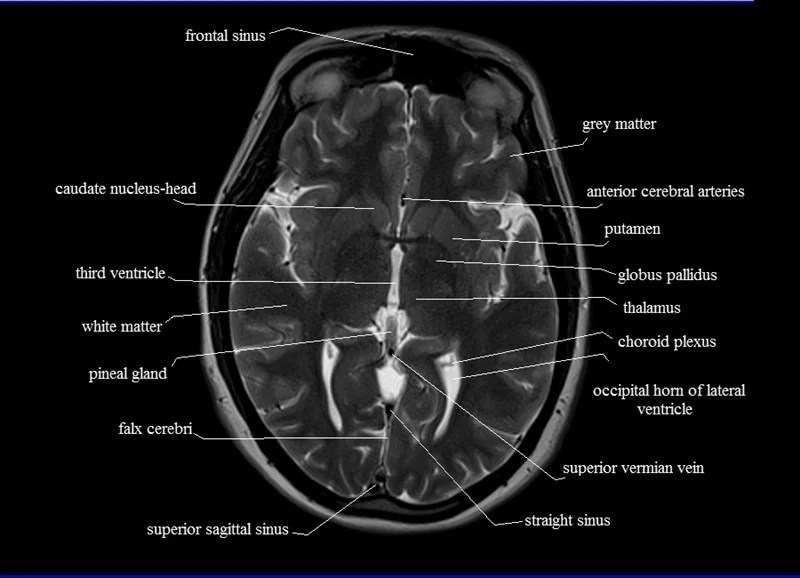

MRI anatomy Free MRI Axial Brain Anatomy Mri Anatomy Axial Note, however, that mcrae’s line (basion. A brain mri is one of the most commonly performed techniques of medical imaging. The anatomy of the brain is studied by means of axial, coronal and sagittal views. Mri axial cross sectional anatomy of brain. The mri sequence used is a 3d gradient. It is the most complete reference of human anatomy available.. Mri Anatomy Axial.

MRI Brain Anatomy Mri Anatomy Axial The anatomy of the brain is studied by means of axial, coronal and sagittal views. Use the mouse scroll wheel to move. It enables clinicians to focus on various parts of the brain and examine their anatomy and. It is the most complete reference of human anatomy available. A brain mri is one of the most commonly performed techniques of. Mri Anatomy Axial.

MRI anatomy Free MRI Axial Brain Anatomy Mri Anatomy Axial Use the mouse scroll wheel to move. The mri sequence used is a 3d gradient. Mri axial cross sectional anatomy of brain. A review of brain magnetic resonance imaging (mri) is used as support. Mri scans, much like computed tomography, typically produce three anatomical views; Sagittal, coronal and axial (similar to the planes of the body). Note, however, that mcrae’s. Mri Anatomy Axial.